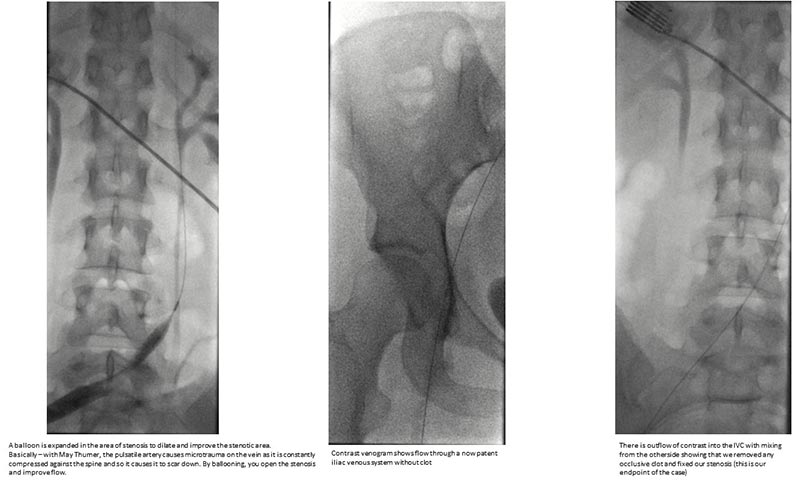

Remnants of the blood clot after the mechanical thrombectomy

We performed a low-dose diagnostic venography and intravascular ultrasound which demonstrated an occlusive thrombus extending throughout the left common iliac vein, left external iliac vein, and left common femoral vein. We accessed the popliteal vein in the back of her knee and used a large bore catheter to debulk the clot from the knee (peripheral) to the lower abdomen (central). We successfully evacuated the clot with minimal residual clot burden seen on post-thrombectomy venography and intravascular ultrasound. Total radiation to the patient and fetus was less than 2 plain film X-rays.

Successful clot evacuation

Successful clot evacuation with minimal residual clot burden seen on post-thrombectomy venography and intravascular ultrasound